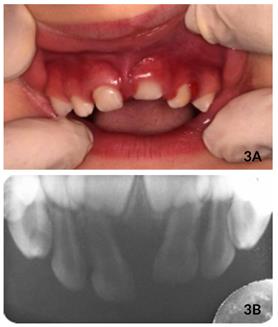

Durante a primeira consulta, foram realizados exames clínico e radiográfico, observando-se inchaço no tecido gengival na região dos incisivos superiores, dentes #61 intruído, com um terço de coroa visível (grau II) e leve intrusão do dente #62, com mais de um terço de coroa visível (grau I) (Figura 1A).

Radiograficamente, (radiografia periapical anterior modificada e radiografia lateral de Fazzi), os dentes #61 e #62 apresentavam- se sem fratura da tábua óssea e lesão dos germes dos dentes permanentes (Figuras 1B e 2). Sendo assim, o tratamento de escolha foi aguardar e acompanhar a reerupção espontânea dos dentes afetados.